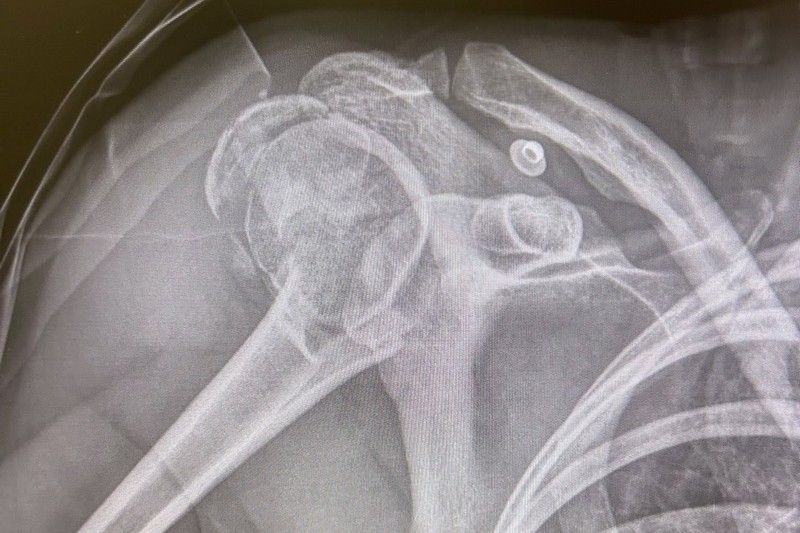

Emmenée sur civière au centre médical du circuit, il lui a été diagnostiqué une fracture de l’humérus droit, ce qui a mis un terme à son week-end. « Accrochage, je me fais couper la route par la 33. Très agressive déjà à la chicane précédent ce virage… Au premier tour elle jouait sa vie va savoir pourquoi ! Comportement… je vais me taire. Merci à tous pour vos messages vraiment. Retour en France pour une opération et je serai à nouveau sur pied, l’histoire ne sera que plus belle », a-t-elle posté sur ses réseaux sociaux.